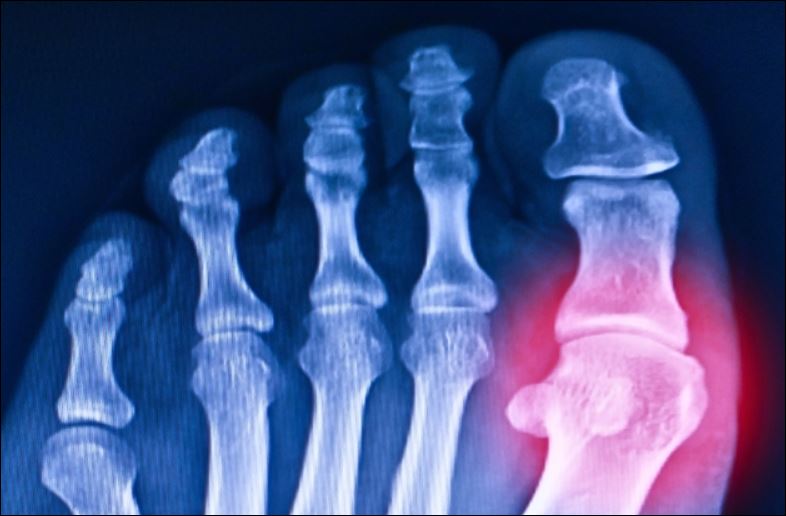

Khi lượng axit uric trong máu quá cao, nó sẽ kết tinh trong các khớp và thận. Từ đó gây ra gout cùng những vấn đề khác như bệnh thận hoặc tổn thương gan. Tình trạng dư thừa này được gọi là tăng axit uric máu (hyperuricemia).

Ảnh minh họa. Nguồn: Tonpor Kasa/Canva.